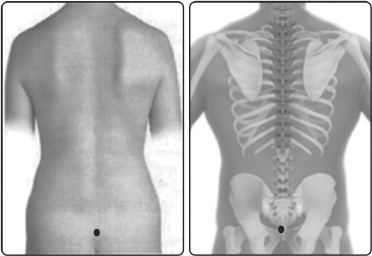

மலப்பிற வர்மம், ஜலப்பிற வர்மத்திற்கும், பூவல் வர்மத்திற்கும் இடையே முதுகுப்பகுதியில் அமைந்துள்ளது. அதாவது மலாசயத்தின் நேர் எதிர்புறம் அமைந்ததே இந்த வர்மம் ஆகும். இவ்வர்மம் மலப்புற வர்மம், மலபந்த வர்மம், சரடு அயர்ந்த காலம் என்னும் வேறுபெயர்களாலும் வழங்கப்படுகிறது.

மலப்பிற வர்மம் என்பது, வன்னெல் எனப்படும் கீழ் முக்கோண எலும்பின் நடுவில் அமைந்ததாகும். அத்தலத்தில் தாக்கம் கொண்டால் வயிறூதும், குடலுக்குள் கழைப்புண்டாகும் என்பதாம்.